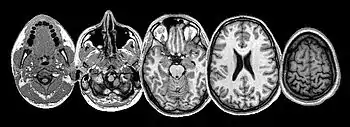

Many brain structures and physiological processes are involved in suffering (particularly the anterior insula and cingulate cortex, both implicated in nociceptive and empathic pain).[28] Various hypotheses try to account for the experience of suffering. One of these, the pain overlap theory[29] takes note, thanks to neuroimaging studies, that the cingulate cortex fires up when the brain feels suffering from experimentally induced social distress, as well as physical pain. The theory proposes therefore that physical pain and social pain (i.e. two radically differing kinds of suffering) share a common phenomenological and neurological basis.